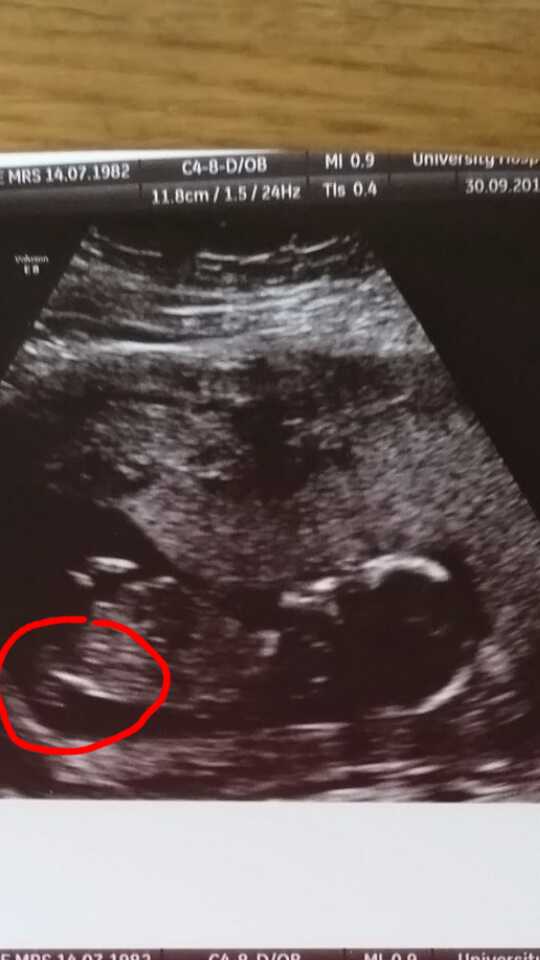

Find it all so interesting but I'm not very good at seeing the clues. Is the centre of the red circle the nub? Or is there not even on in this pic?

No clear nub. You circled the spine.

You got to look higher for a nub. Its were the boy/girl parts develop.